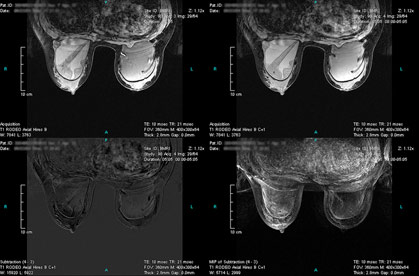

Case 3 - Left breast with 2 cancer sites

(from left to right, top to down)

RODEO Pre (unspoiled), Registered 1st Post (spoiled), TIC of the 1st ROI and MIP of Subtraction.